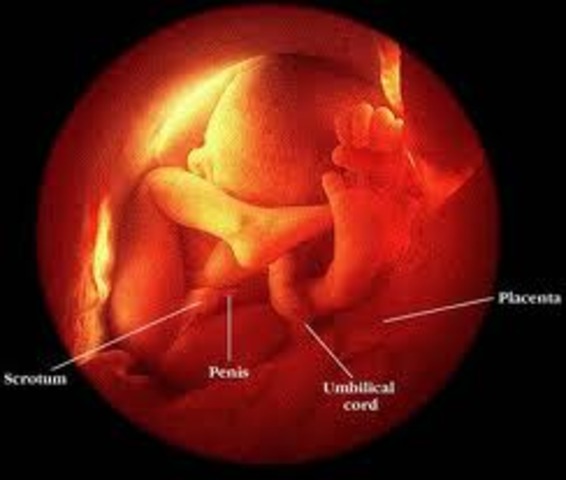

• Week 20

Week 20

Your baby weighs about 10 1/2 ounces now. He's also around 6 1/2 inches long from head to bottom and about 10 inches from head to heel — the length of a banana. (For the first 20 weeks, when a baby's legs are curled up against his torso and hard to measure, measurements are taken from the top of his head to his bottom — the "crown to rump" measurement http://www.babycenter.com/6_your-pregnancy-20-weeks_1109.bc